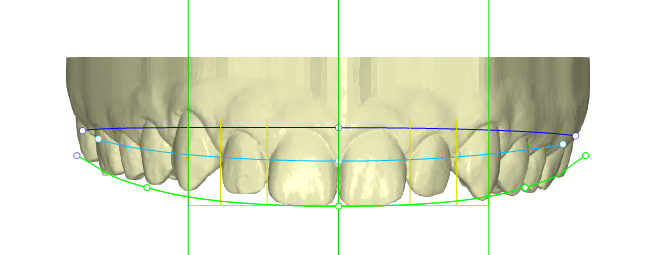

Paciente joven que acababa de finalizar su tratamiento de ortodoncia. Aunque estaba satisfecho con el resultado general, no se sentía cómodo con las troneras incisales que habían quedado entre los laterales y los caninos. Buscaba una solución rápida, estética y mínimamente invasiva

Desde Elevantia Solutions propusimos un Injectable Composite Design con carillas únicamente en esas piezas, para cerrar los espacios sin necesidad de limar sus dientes. Se trabajaron varias versiones del diseño hasta conseguir un resultado totalmente adaptado a sus expectativas, respetando al máximo la estructura dental natural al cerrar los espacios